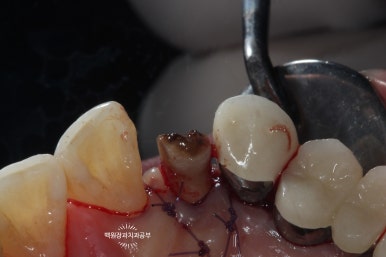

왼쪽: periotome을 사용하여 발치 시행, 오른쪽: 치아를 완전히 뽑지 않고 위치를 수정.

치아를 약간 정출시킨 후 봉합사를 이용하여 고정해줍니다.

보시는 바와 같이 치아를 약간 정출시켜줍니다. 대개는 2-3mm 정도 정출시킵니다.

그렇기 때문에 뿌리가 너무 짧은 치아는 이러한 외과적 정출술이 불가능합니다.

오른쪽 사진을 보시면, 입천장 쪽에서 보았을 때 치아가 보다 더 정출한 것을 보실 수 있어요.